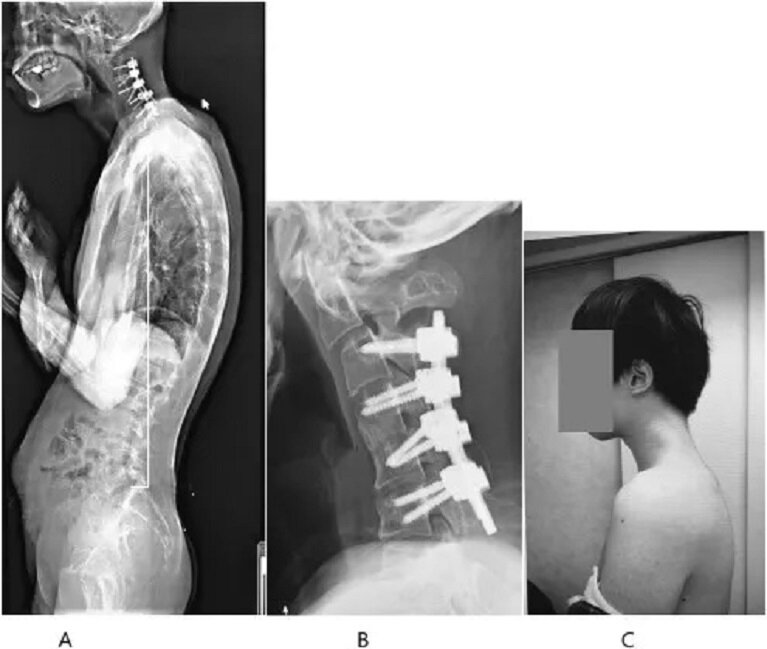

日本醫學病例報告,揭示長時間低頭玩智能手機可能引發嚴重的「頭部下垂症候群」(Dropped Head Syndrome)。報告指出,一名 25 歲男子因長期沉迷手機遊戲,頸部肌肉嚴重衰弱,無法抬頭,頸椎更出現異常膨出。醫生警告,隨著年輕人智能手機使用時間激增,類似健康風險極需關注。

頸椎 90 度畸形 後頸凸硬塊

據《JOS Case Reports》2023 年刊載的報告,這名患者因頸部劇痛六個月及無法抬頭,由於吞嚥困難、每日僅能進食一餐,體重亦逐漸下降,同時出現上肢麻木、左手無力等問題,男子依然堅持獨自忍痛半年,才願意求醫。醫生檢查發現,其頸椎因長期處於不自然姿勢「極度伸展」,形成畸形,並伴隨瘢痕組織。掃描顯示,患者頸椎骨骼扭曲錯位,頸部膨出一塊異物。

以頸托治療無效 終做手術矯正

報告續指,醫生最初嘗試以頸托矯正患者姿勢,但患者因佩戴時感到麻痺而中止治療。最終,醫生選擇手術方案,先移除部分頸椎小骨片及瘢痕組織,再於頸椎植入螺絲及金屬棒以矯正姿勢。術後六個月,患者能輕鬆保持頭部水平,一年後隨訪顯示抬頭及吞嚥問題未復發,顯示治療成功。